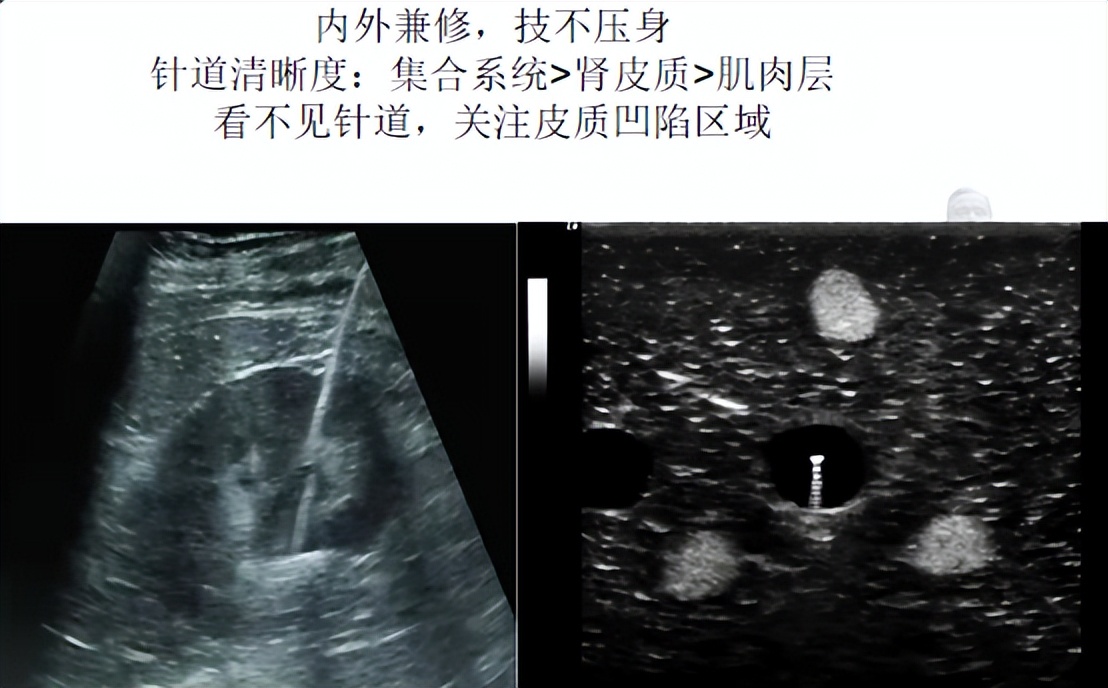

B超引导穿刺有平面内和平面外两种手段。B超探头与皮肤一面之缘,要求:1.垂直,不偏不倚;2.紧贴,相依相靠。

平面内:相向而行、有迹可寻。平面内穿刺是关键领域亮剑,将目标肾盏置于和超声左侧扇面边缘成30°处,盏颈同轴一见倾心,只见云来遮、雾来盖,云里雾里放光彩。

平面外:若隐若现、抛头露面。平面外穿刺为敏感部位*点露**,以目标肾盏垂直对应的探头侧方皮肤作为穿刺点,紧贴探头进针。关注目标动静,扶墙(通道)花影动,疑是玉人(针芯)来。李商隐体会心有灵犀一点通,说的是使出灵犀一指开路,抵达目标肾盏点到为止。

日立超声具有全球独一无二的零角度穿刺探头,探头中间内置一次性穿刺架,易于剥离探头不影响穿刺针及导丝进出,并且探头厚度薄,可避开肋骨和穿刺路径的血管,通过肾盏穹窿部精准穿刺。此物在手,只要看上肾脏后宫哪位佳丽,便垂手可得全不费工夫。

望穿秋水,水到渠成。穿刺到位的标志是拔芯见水。水不出来,或许是穿刺针与集合系统还有隔膜,不捅破这层膜,导丝就尚未和肾脏发生关系。肾积脓也可能抽不出水,可以通过注水回抽鉴别。一句话,没湿别冒进。

导丝有了立锥之地,就要顺势而为。扩张谨记知根知底、边推边挤、导丝引领、稳步徐行。穿刺针到位即可测量皮肾通道深度,实际深度并非一成不变,需体谅肾不由己,受到外力推挤、肾脏活动度等多因素影响。

方哥有话说。 导丝到位,鞘是否置入集合系统有四招验证。1.鞘芯触及导丝前端有摩擦感(导丝打折则不可行)。2.扯动导丝有无阻力感(导丝打折则不可行)。3.留芯进鞘有无阻力感(鞘进集合系统顺畅)。4.退芯鞘内置入输尿管导管(对比扩张鞘长度)。遭遇不动如山、寸步难移的铸型结石,哥哥你大胆地往前走,一杆子到底不回头。

B超引导下穿刺开路就那么回事:(探头)下盘要稳,进针要准,置鞘要顺。跟着导丝走,肾脏在招手。见好就穿,见缝就钻,屡试不爽。